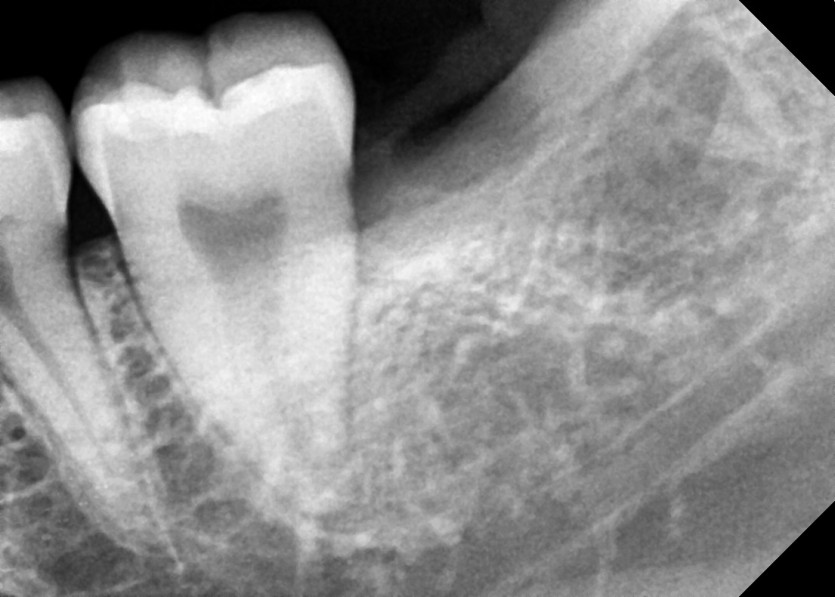

#38 사랑니 발치

구강 외과 전문의가 당일 발치했습니다.